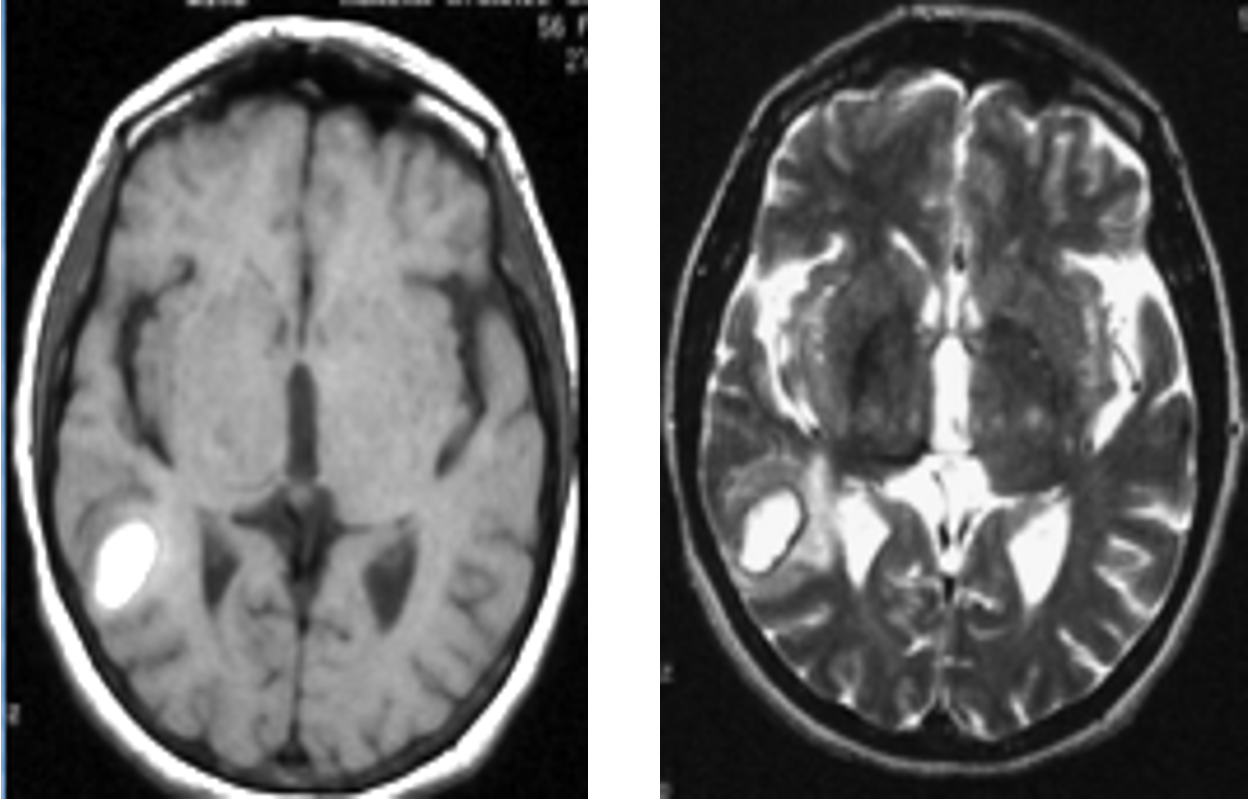

Subacute Hematoma